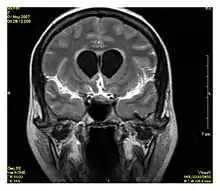

Neuroimaging

MRI diffusion tensor imaging of white matter tracts

MRI is the investigative tool of choice for neurological cancers over CT, as it offers better visualization of the posterior cranial fossa, containing the brainstem and the cerebellum. The contrast provided between grey and white matter makes MRI the best choice for many conditions of the central nervous system, including demyelinating diseases, dementia, cerebrovascular disease, infectious diseases, Alzheimer's disease and epilepsy.[20][21][22] Since many images are taken milliseconds apart, it shows how the brain responds to different stimuli, enabling researchers to study both the functional and structural brain abnormalities in psychological disorders.[23] MRI also is used in guided stereotactic surgery and radiosurgery for treatment of intracranial tumors, arteriovenous malformations, and other surgically treatable conditions using a device known as the N-localizer.[24][25][26]